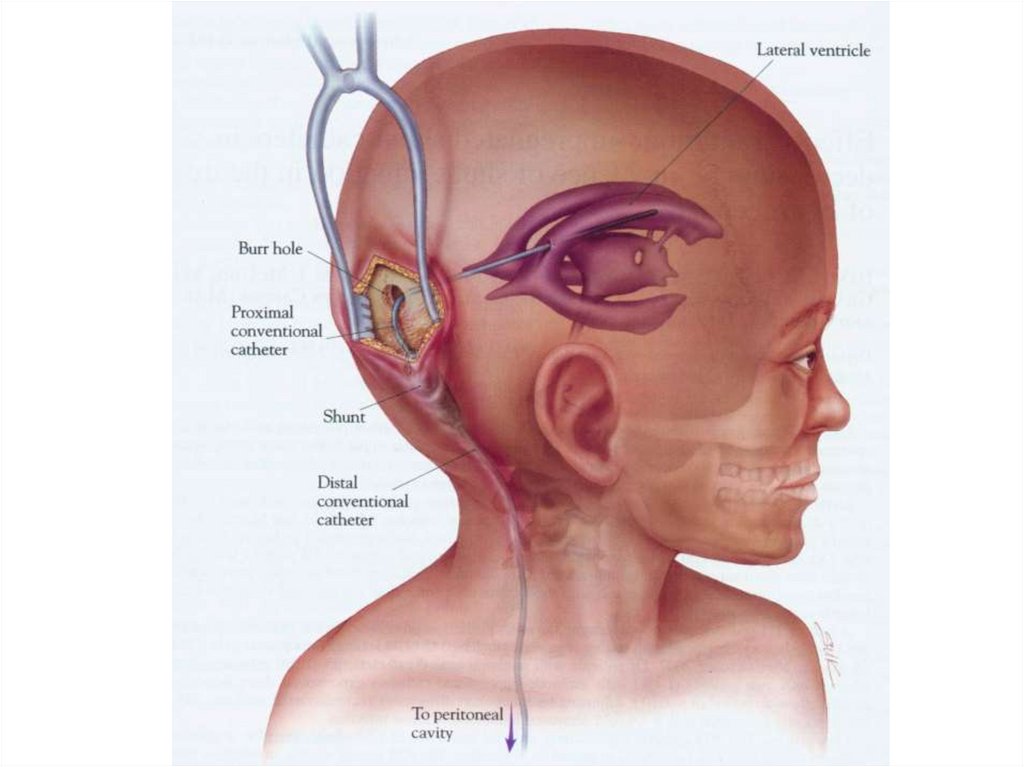

Внутричерепная гипотензия: КТ-исследования и их интерпретация

Раздел: Образы вокруг